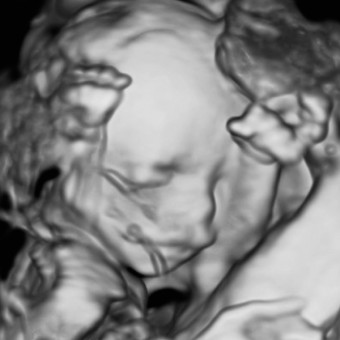

Baby Boy Broadley

Alex Curtiss

July 13, 2026